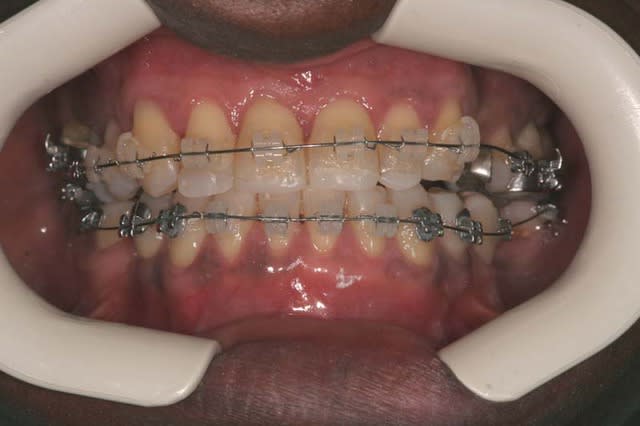

l’overjet se réduit (lentement)

5 ynbzmb - Eugenol

Je rajoute un Q.H. Crozat

6 qzips3 - Eugenol

Je peux alors mettre un arc Inf.

8 uqmptf - Eugenol